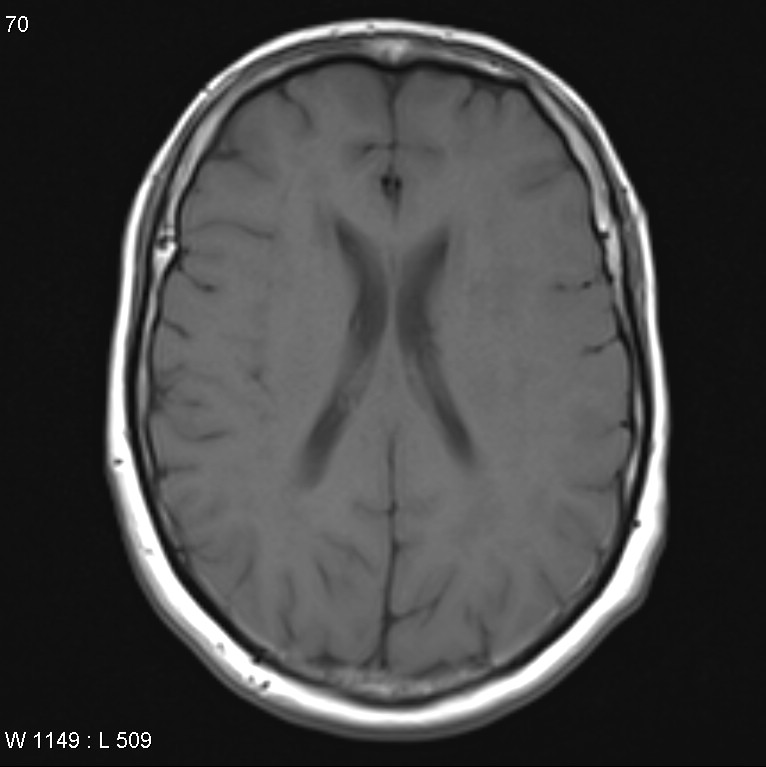

Болезнь Нимана-Пика Тип А: Симптомы и лечение

Раздел: Визуальный дайджест